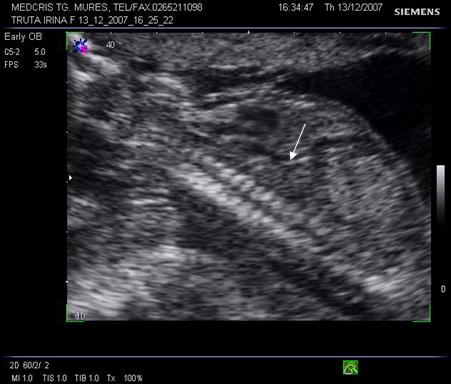

Primele ecografii Doppler in sarcina cu antecedente patologice incep la 22 - 24 saptamani si se repeta la 28 - 32 sapt., sau chiar mai repede in cazul depistarii unor unde anormale.

Aspecte patologice anormale ale examenului Doppler ombilical

Daca rezistenta placentara creste, viteza reziduala in diastola se reduce, iar IR si IP cresc.

Aspectul IR este patologic peste percentila 90 din curba de referinta, daca frecventa cardiaca fetala este normala. De asemenea, daca doua examinari la 4 sapt. interval indica o stagnare a IR sau o scadere a fluxului diastolic, situatia este patologica.

In situatii de rezistenta placentara si mai crescuta, se poate ajunge la flux diastolic absent, sau componenta diastolica negativa (reverse flow) ceea ce indica o alterare grava a hemodinamicii fetoplacentare. [3,14,17]